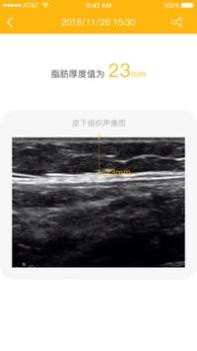

1、提供清晰的皮下组织超声图,不仅为用户提供数据检测结果,还同步导入皮下组织的超声图像;

2、清晰的图片厚度标记,在超声图像中也勾画出对应的脂肪厚度线和对应的数据标记;